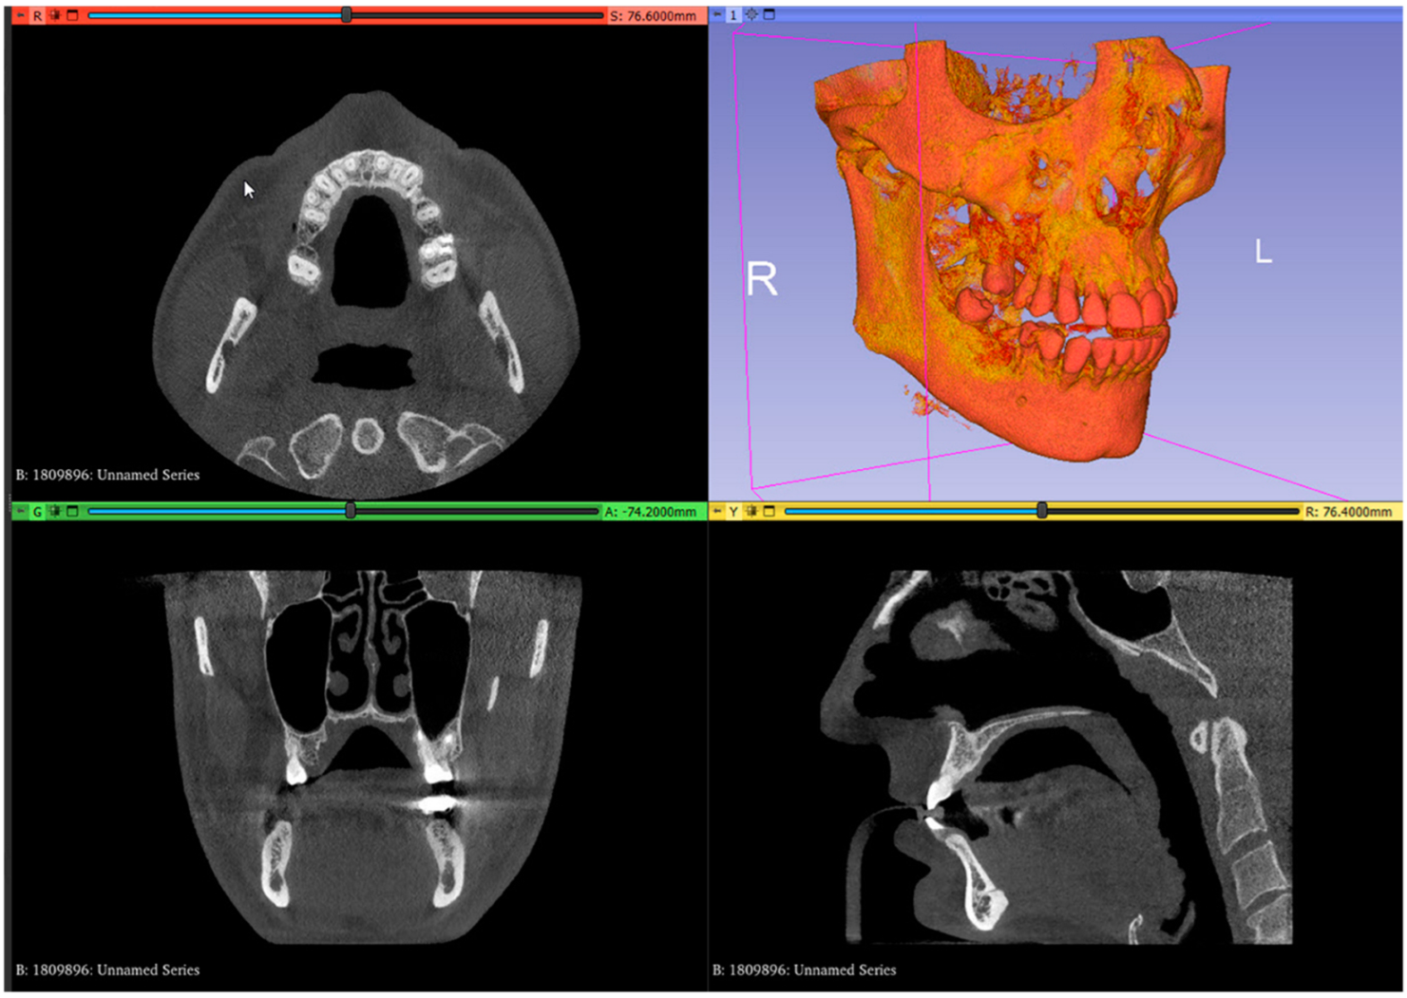

- Set up the Hounsfield scale at a lower value for a better view of the posterior palatal area on the 3D reconstruction by using the specific shift tool (Display: Shift). The value must be set at 150 HU. Change the module from volume rendering to segment editor (Modules: Segmentation Editor). Perform the first segmentation of the maxillary bone by using the “Threshold” tool (Figure 1);